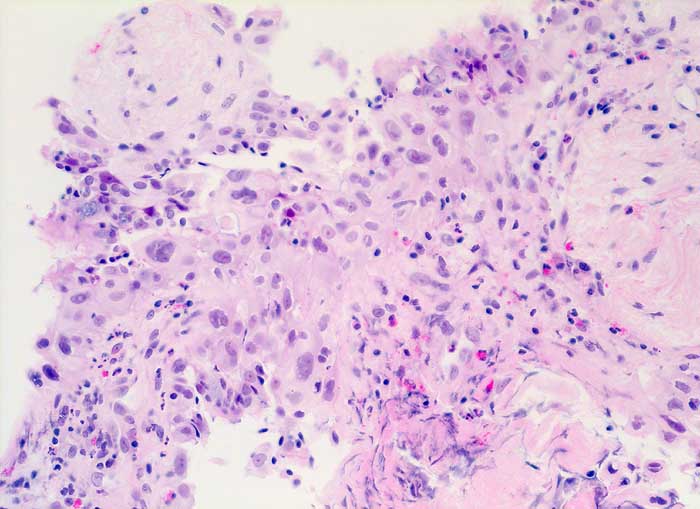

strahleninduzierte Kernatypien

Ausgeprägte Kernpolymorphie und Kernvergrösserung des respiratorischen Epithels bei erhaltener Kern-Zytoplasmarelation.

NSCLC neoadjuvante Therapie

200